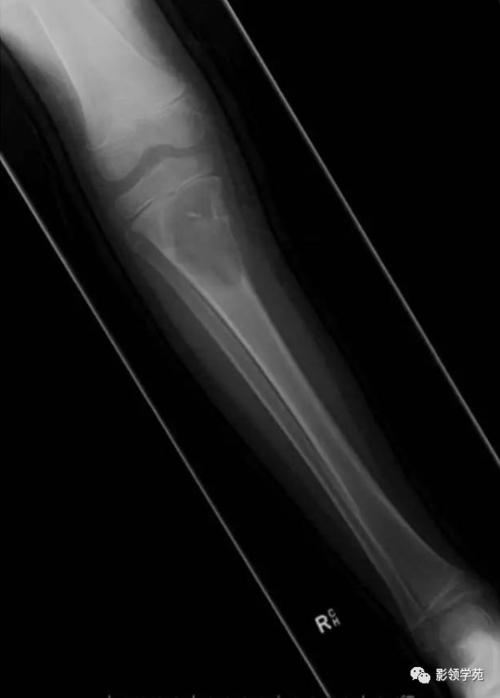

骨囊肿影像,股骨骨囊肿

股骨骨囊肿

骨囊肿

骨囊肿ct

小腿骨囊肿